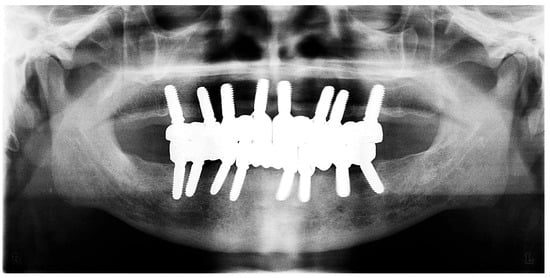

Figure 15. Panoramic X-ray showing the final prostheses (taken 21 November 2023).

The restoration plan involved placing a bridge that connects the central incisors to the canines, along with an additional bridge spanning the first premolar to the first molar on each side of the maxillary arch. In the mandibular arch, the plan included three bridges: one connecting the lateral incisors bilaterally and another bridging the canines to the second premolars and first molars on each side (Figure 14 and Figure 15). Placing was confirmed using Panoramic radiographs obtained using the PantOs DG XP panoramic dental X-ray system (Fona S.r.l., Assago, Italy; CE 0051). The unit operates on a 230 V, 50/60 Hz input line with an 8 A fuse. Standard panoramic exposure parameters were applied (90 kVp, 10 mA, exposure time 14 s) following the manufacturer’s safety recommendations. A trained radiology technician performed all scans, and patient positioning was standardized using the built-in cephalostat support and light-beam alignment to ensure reproducibility of serial images.